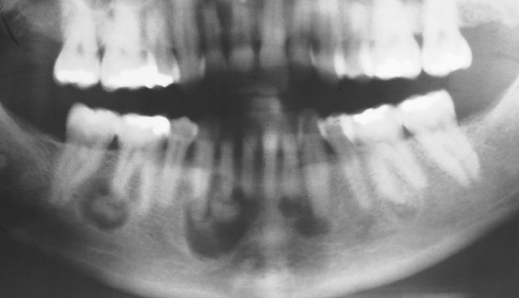

periapical cemento-osseous dysplasia

focal cemento-osseous dysplasia